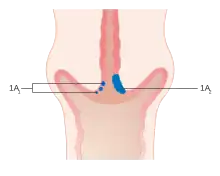

-

Stage 1A cervical cancer -